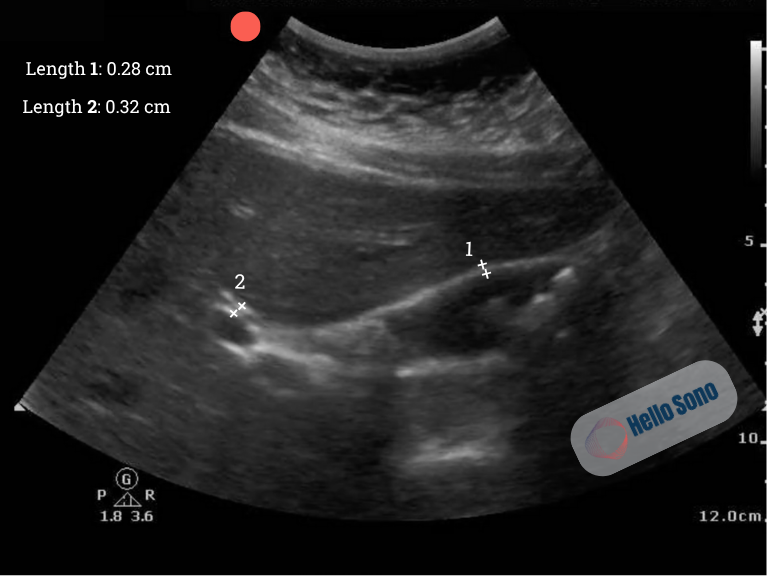

Ultrasound image of the gallbladder in the long plane. Length 1 is the anterior gallbladder wall diameter (AGWD), and length 2 is the common bile duct (CBD) diameter. Hyperechoic stones with posterior acoustic shadows are seen.

Image 1: Ultrasound image of the gallbladder in the long plane. Length 1 is the anterior gallbladder wall diameter (AGWD), and length 2 is the common bile duct (CBD) diameter. Hyperechoic stones with posterior acoustic shadows are seen.

POCUS reveals hyperechoic structures within the gallbladder lumen that cast posterior acoustic shadows, consistent with gallstones. The gallbladder wall is thin, measuring 0.28 cm, and the CBD is normal at 0.32 cm.  There is no pericholecystic fluid, and the sonographic Murphy’s sign is negative. The stones are mobile when the patient’s position changes.

These findings support cholelithiasis without cholecystitis.